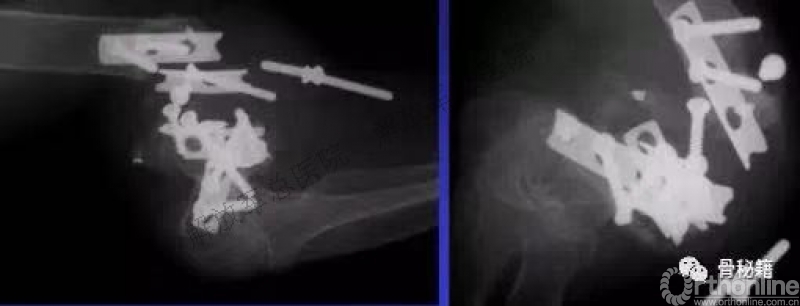

看看这些失败的case,肱骨远端不简单!